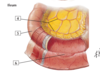

1

1 - superior mesenteric artery

2

2 - middle colic artery

3

3 - straight arteries (arteriae rectae)

4

4 - marginal artery

5

5 - right colic artery

6

6 - ileocolic artery (colic branch, ileal branch)

7

7 - appendicular artery

8

8 - superior rectal artery

9

9 - sigmoid arteries

10

10 - left colic artery

11

11 - inferior mesenteric artery

12

12 - jejnal and ileal (intestinal) arteries